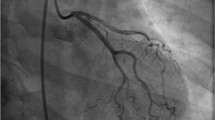

Since SCAD patients present with symptoms of acute coronary syndrome (ACS), the most utilized diagnostic tool is coronary angiography. The left anterior descending (LAD) artery is the most frequently affected vessel in SCAD, though multivessel involvement can occur in up to 15% of cases [1, 26•]. The Yip-Saw classification outlines three angiographic subtypes of SCAD, distinguishing between these subtypes provides valuable insight to assist with clinical decision-making and management.

Type 1 is characterized by a dual-lumen sign, occurring when the true and false lumen can be simultaneously visualized due to a communicating fenestration [26•]. This finding is pathologically distinct from the other Yip-Saw subtypes as it represents a later stage of dissection and often signifies a lower risk for progression [21, 26•]. Meanwhile, only the true lumen can be appreciated in type 2 and 3 lesions. Type 2 is the most common angiographic finding, described as a tapering, diffuse, and smooth stenosis with a typical lesion length of > 20–30 mm [21, 27]. These lesions will not improve with the administration of intracoronary nitroglycerin [27]. Type 3 lesions, reported in a minority of cases, appear to be focal and can be easily misdiagnosed as atherosclerotic disease [27]. Pretest probability for atherosclerotic disease is key in identifying SCAD in patients presenting with type 3 lesions [1, 26•]. The addition of a type 4 lesion, being complete vessel occlusion, has been proposed to the current classification system, and further modifications may be needed as SCAD becomes increasingly identified on angiogram [26•].

At the time of angiogram, a prior cohort study by Saw et al. demonstrated that culprit lesions had an average stenosis of 78.7% with a measured dissection length of 45–48 mm, representing a longer lesion length when compared to atherosclerotic disease [16, 26•]. Thrombolysis In Myocardial Infarction (TIMI) flow 3 was present in slightly over 50% of the cases on initial angiography [27]. Another angiographic review demonstrated increased coronary artery tortuosity, defined as the presence of three or more consecutive vessel curvatures of 90–180° when compared to patients presenting for ACS from alternative etiologies [18]. Increased vessel tortuosity was most frequently appreciated within the left circumflex artery and was observed more frequently in non-culprit arteries [18].

Angiographic findings must be considered in the context of patient age, gender, and medical history. Additional angiographic clues to assist in the diagnosis of SCAD include otherwise minimal atherosclerotic disease and vessel tortuosity [18]. Differentials that must be considered include iatrogenic vessel dissection, atherosclerotic disease, coronary vasospasm, takotsubo cardiomyopathy, myocardial bridging, and embolization [26•]. When the diagnosis is uncertain, alternative intracoronary imaging modalities such as optical coherence tomography (OCT) or intravascular ultrasound (IVUS) may be helpful [9, 26•, 28, 29••].